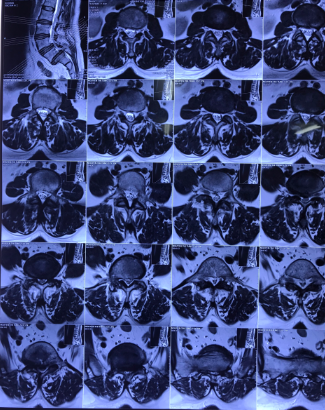

Hình ảnh: Cộng hưởng từ và X Quang bệnh nhân trước phẫu thuật

Bệnh nhân Nguyễn Thị T. (53 tuổi) tại Nghi Thuỷ - TX Cửa Lò xuất hiện tình trạng đau cột sống thắt lưng đã lâu, được điều trị bằng Y học cổ truyền và Phục hồi chức năng nhiều năm nay. Hiện tại, tình trạng đau tăng lên, đau tê dọc 2 chân, đi lại khó khăn, cơ lực 2 chân giảm. Sau khi tìm hiểu tham khảo nhiều đơn vị khác, chị T. được giới thiệu tới bệnh viện CTCHNA thăm khám và được chẩn đoán trượt đốt sống thắt lưng L5 độ III, thoát vị đĩa đệm L5S1 gây hẹp ống sống nặng, chèn ép rễ thần kinh L5 hai bên.